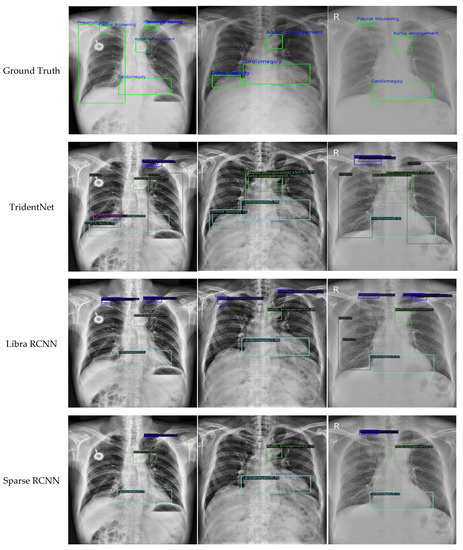

For an objective evaluation of our approach, three popular approaches (i.e., cascade R-CNN [43], TridentNet [44], and Libra R-CNN [45]) and two of the latest approaches (Sparse R-CNN [46] and Swin Transformer [18]) were selected for comparison, all of which achieved the state of the art in object detection while publishing. For the experimental parameters of the compared methods, we used the best configuration recommended by the mm-detection toolbox. Specifically, for cascade R-CNN, TridentNet, and Libra R-CNN, the initial learning rate, momentum, and weight decay were set to 0.02, 0.9, and 0.0001, respectively, and the SGD optimizer was employed to regulate the learning rate; for Sparse R-CNN and Swin Transformer, the initial learning rate and weight decay were set to 0.000025 and 0.0001, respectively, and the AdamW optimizer was employed. For the sake of a fair comparison, the proposed method used the same parameters with cascade R-CNN, TridentNet, and Libra R-CNN, since the parameters they required were similar. In addition, in terms of the convergence criteria, the batch size and training period were set to 2 and 12, respectively, for all compared methods. The AP and mAP of the compared methods in the VinDr-CXR dataset are listed in Table 2, where the values marked in bold indicated the best performance. The P–R diagrams of some representative abnormal categories for the compared methods are shown in Figure 7. To demonstrate the effectiveness of the proposed approach more intuitively, detection examples of the compared methods are shown in Figure 8.

Figure 8.

Detection examples of the compared methods.

The following findings were obtained from the above experimental results.

First, the proposed method achieved the highest mAP of 0.362, which was 3.2% higher than that of cascade R-CNN (baseline) and 4.8%, 5.6%, 11.3%, and 2.6% higher than that of TridentNet, Libra R-CNN, Sparse R-CNN, and Swin Transformer, respectively. Second, different models were suitable for different types of chest anomaly detection, but our model achieved the highest AP in most categories; that is, we achieved the best performance in five out of the fourteen categories. For example, Libra R-CNN achieved a superior detection precision in pleural effusion, whereas Sparse R-CNN was suitable for detecting large-scale chest abnormalities such as aortic enlargement. Another recently published method that has to be mentioned is Swin Transformer, which showed good potential in the anomaly detection of chest X-rays and achieved the highest AP in three categories, i.e., calcification, pneumo-thorax, and pulmonary fibrosis. However, the proposed method achieved the best results in most categories, including large-scale and small-scale abnormalities, such as infiltration, atelectasis, pleural thickening, consolidation, and cardiomegaly.

Second, by observing the anomaly detection examples shown in Figure 8, visual comparisons also proved that the proposed method generally achieved more accurate detection results, and that our approach could effectively identify the specific locations of various types of chest anomalies. Even for small targets, our method exhibited a high degree of coincidence with the ground truth. This was mainly due to the fact that we improved the backbone networks with embedded local features and context information. Moreover, with the optimized feature fusion process, information from different scales was rationally used to obtain a more accurate prediction region.